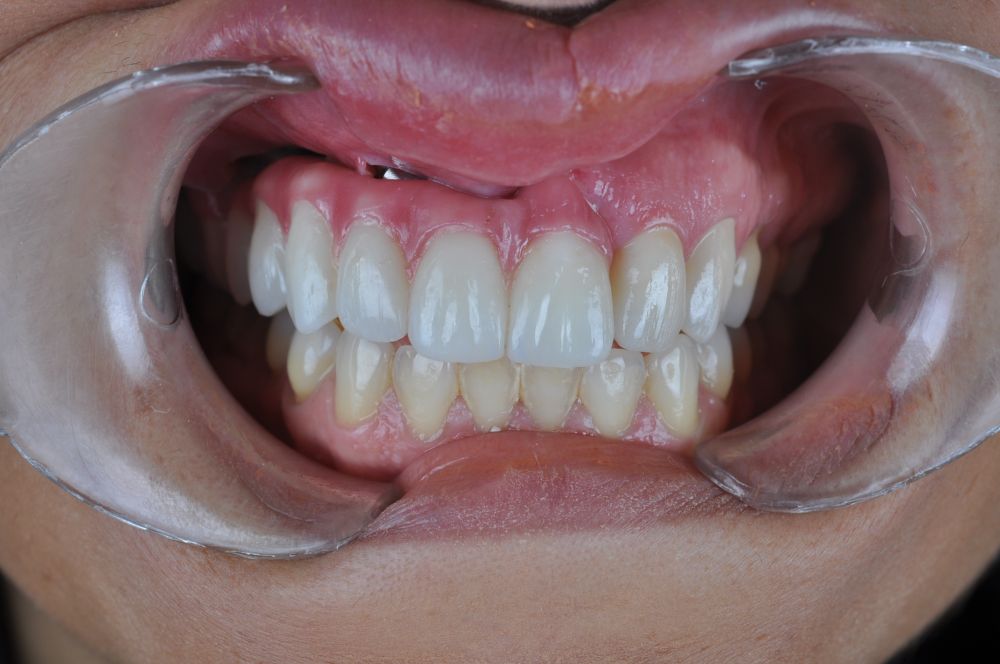

Para la fabricación de las estructuras, se eligió el óxido de zirconio monolítico como material restaurador sobre interfases metálicas en el puente implantosoportado, y coronas de óxido de zirconio monolítico en los dientes tallados previamente (1.7, 1.6, 2.2 y 2.3). Se tomaron impresiones de cubeta abierta con silicona de adición pesada y fluida (Zhermack Elite HD, Gmbh). Se realizó una prueba de pasividad analógica y el resto del proceso se confeccionó de manera digital, por lo que se hicieron pruebas estéticas de dientes impresas en 3D sobre interfases metálicas, para hacer todos los ajustes de función y estética previos al fresado del zirconio monolítico (Figuras 11, 12 y 13).

El día de la colocación de las estructuras, se arenó el interior de las coronas dentosoportadas con óxido de aluminio de 50 m y fueron cementadas con cemento de resina Multilink Ò. El puente implantosoportado se atornilló al torque indicado (20Nw) (Figuras 14, 15, 16 y 17).

Las impresiones analógicas y el posterior flujo digital permitieron una correcta planificación protésica. Las estructuras definitivas, confeccionadas en óxido de zirconio monolítico sobre interfases metálicas de titanio, mostraron una adecuada adaptación pasiva tanto clínica como radiográficamente. La prueba estética permitió ajustes oclusales y funcionales mínimos, optimizando el resultado final.

En enero de 2021, el puente implantosoportado fue atornillado con un torque controlado (20 Nw), y las coronas dentosoportadas cementadas con éxito. La paciente refirió una notable mejoría en la función masticatoria, fonación y estética facial, manifestando un alto grado de satisfacción.